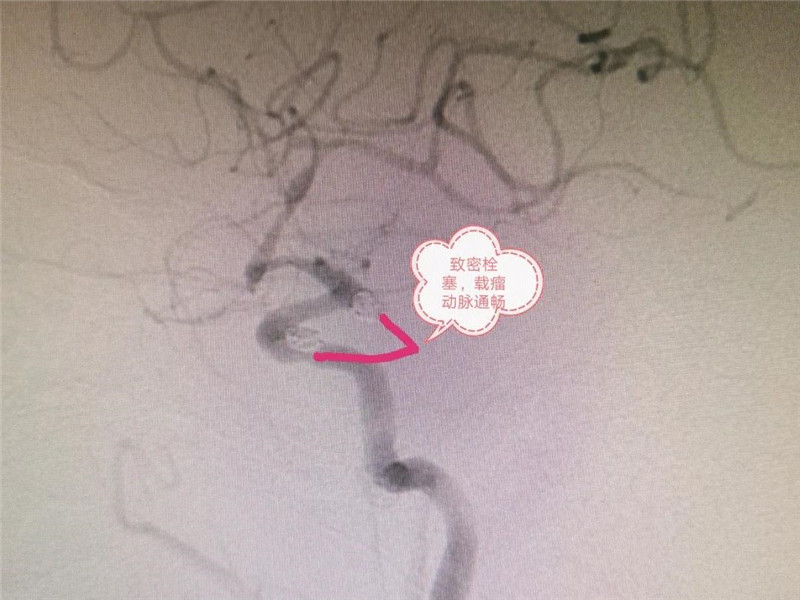

脑动脉瘤破裂三天后才“发现”,医生手术2个半小时助其康复

李姨说:“三天前,我出现过头痛、头晕,以为是普通感冒,就随便吃了点感冒药。要不是医生检查,我真不知道是脑动脉瘤破裂!”4月底,工作时突然头痛头晕,双腿乏力倒地的55岁李姨被紧急送至三水区人民医院接受手术。经卒中中心专家团队2个半小时脑动脉瘤...